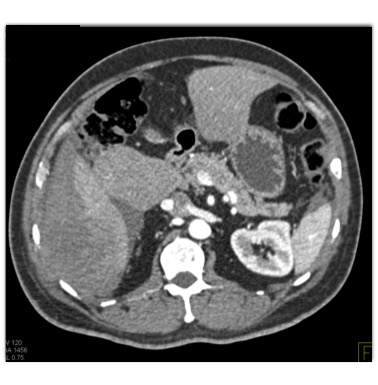

In this patient with RUQ pain the least likely diagnosis is?

hepatic adenoma

hepatoma

metastatic neuroendocrine tumor

hemangioma